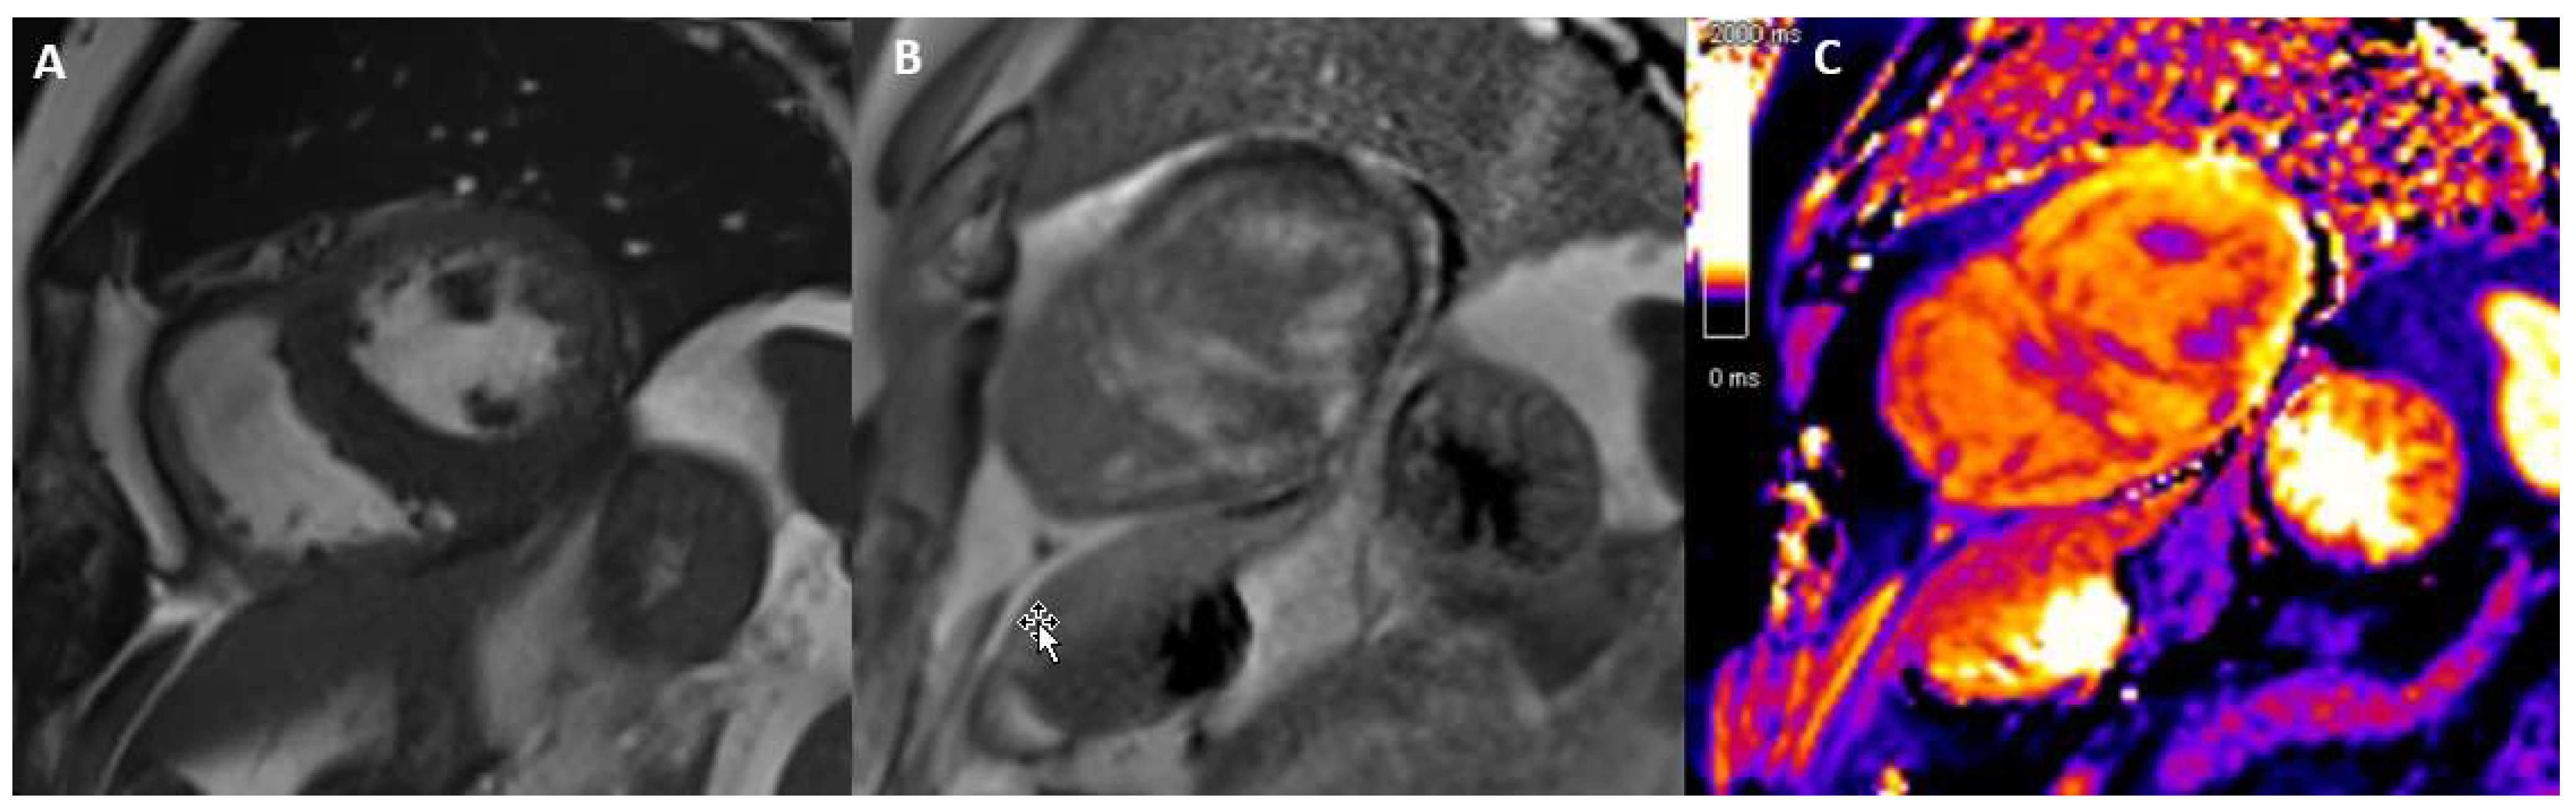

3.7. Cardiac Sarcoidosis

- Greulich, S.; Kitterer, D.; Latus, J.; Aguor, E.; Steubing, H.; Kaesemann, P.; Patrascu, A.; Greiser, A.; Groeninger, S.; Mayet, A.; et al. Comprehensive cardiovascular magnetic resonance assessment in patients with sarcoidosis and preserved left ventricular ejection fraction. Circ. Cardiovasc. Imaging 2016, 9, e005022. [Google Scholar] [CrossRef]

- Slart, R.H.J.A.; Glaudemans, A.W.J.M.; Lancellotti, P.; Hyafil, F.; Blankstein, R.; Schwartz, R.G.; Jaber, W.A.; Russell, R.; Gimelli, A.; Rouzet, F.; et al. Document Reading Group. A joint procedural position statement on imaging in cardiac sarcoidosis: From the Cardiovascular and Inflammation & Infection Committees of the European Association of Nuclear Medicine, the European Association of Cardiovascular Imaging, and the American Society of Nuclear Cardiology. J. Nucl. Cardiol. 2018, 25, 298–319. [Google Scholar] [CrossRef]

- Hulten, E.; Agarwal, V.; Cahill, M.; Cole, G.; Vita, T.; Parrish, S.; Sommer Bittencourt, M.; Murthy, V.L.; Kwong, R.; Di Carli, M.F.; et al. Presence of late gadolinium enhancement by cardiac magnetic resonance among patients with suspected cardiac sarcoidosis is associated with adverse cardiovascular prognosis: A systematic review and meta-analysis. Circ. Cardiovasc. Imaging 2016, 9, e005001. [Google Scholar] [CrossRef]

- Coleman, G.C.; Shaw, P.W.; Balfour, P.C.; Gonzalez, J.A.; Kramer, C.M.; Patel, A.R.; Salerno, M. Prognostic value of myocardial scarring on CMR in patients with cardiac sarcoidosis: A systematic review and meta-analysis. JACC Cardiovasc. Imaging 2017, 10, 411–420. [Google Scholar] [CrossRef]